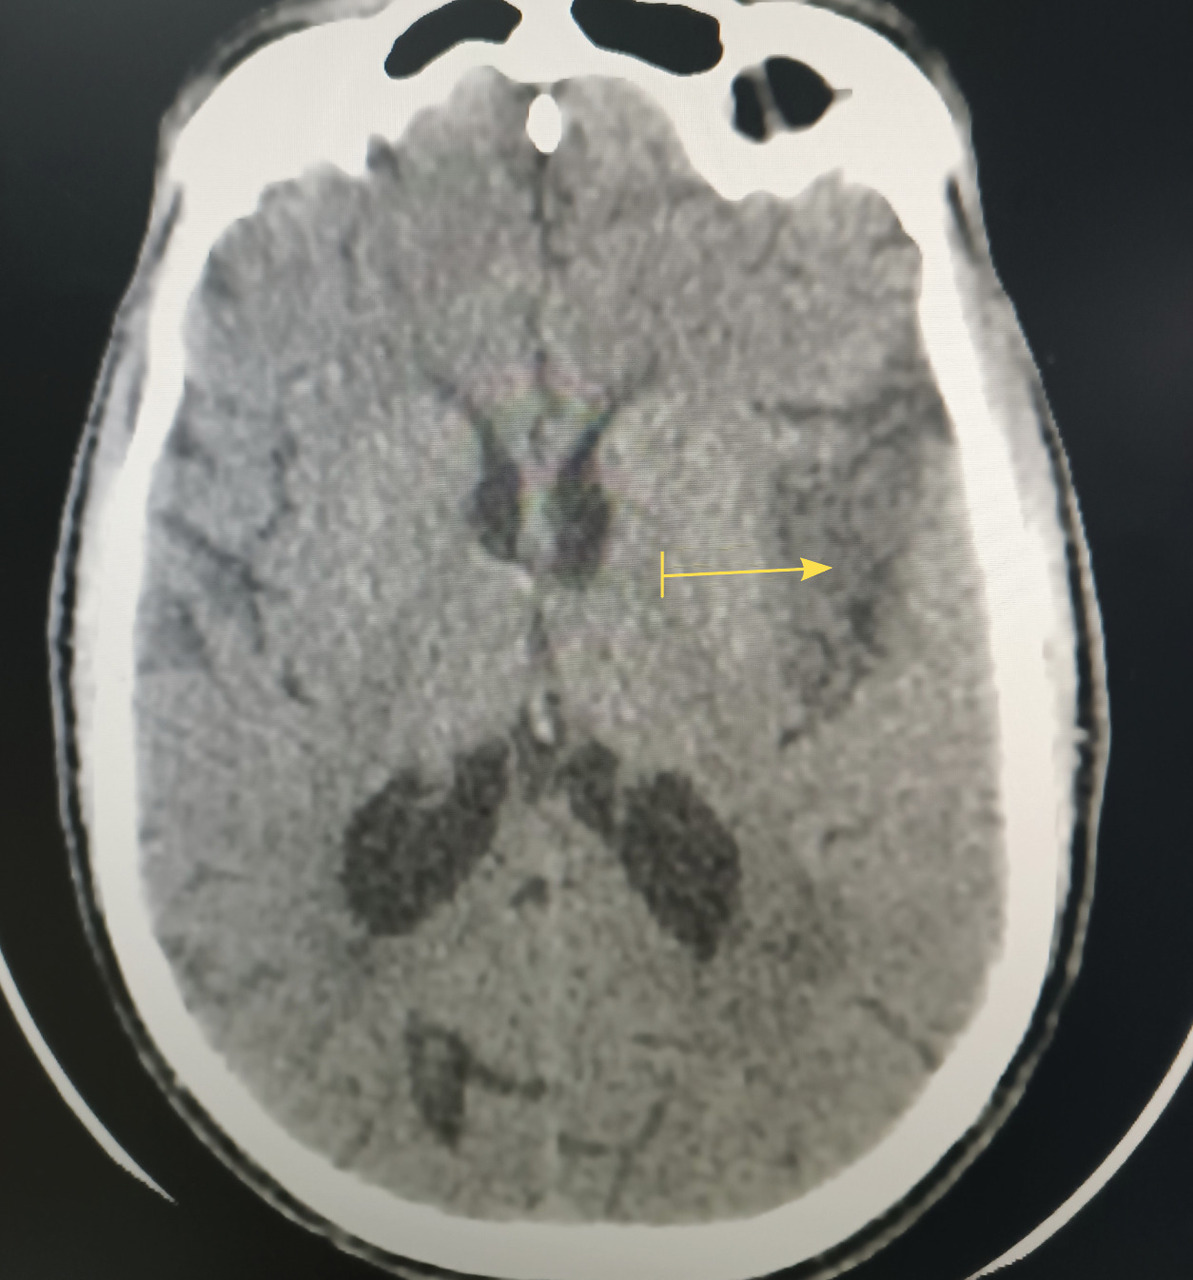

Le scanner cérébral révèle un accident vasculaire cérébral ischémique du territoire de l’artère cérébrale moyenne superficielle gauche (fig. 1).